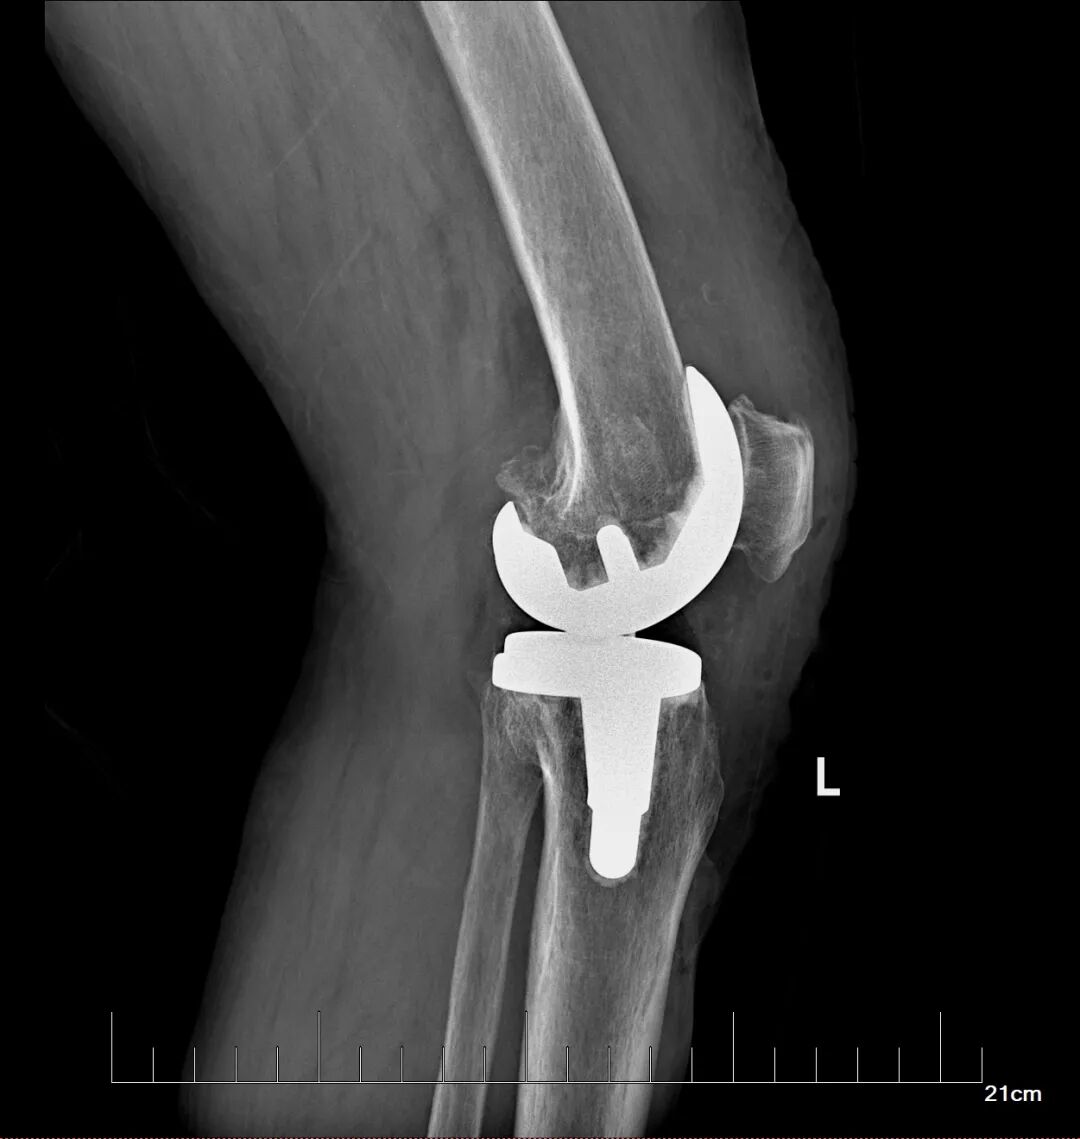

在充分的术前准备基础上,骨科蔡志荣主任带领团队,为李女士实施了左侧全膝关节置换术。团队凭借精湛的操作技术,精准完成了假体植入与软组织平衡,术中出血量仅30毫升,无需输血,患者生命体征平稳。得益于“快速康复外科”理念的应用,李女士在术后第二天就能在助行器辅助下站立并行走。恢复速度远超传统关节置换术后的康复进程,患者及家属对治疗效果赞不绝口。